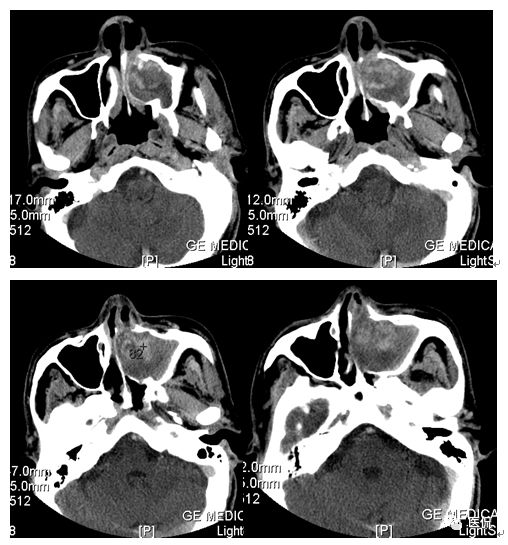

影像资料

冠状位平扫

增强动脉期

CT平扫及增强示:左侧上颌窦及鼻腔可见软组织密度影,呈膨胀性生长,周围骨质压迫性吸收破坏,累及左眶,病灶密度不均匀,周边区可见点状钙化,增动脉期轻度强化,局部见小灶性稍高密度区,静脉期病灶内见不均匀明显强化,CT值最高达117HU,延迟期强化范围有所增大。

本例病灶较大,周围骨质可见吸收破坏,并累及眼眶,病灶内少量钙化,增强扫描具有一定特征性,表现为动脉期轻度强化,局部见小灶性稍高密度区,静脉期病灶局部呈明显强化,CT值最高达117HU,延迟期强化范围有所增大,呈延迟渐进性强化的特点,推测为病灶内出血所致。